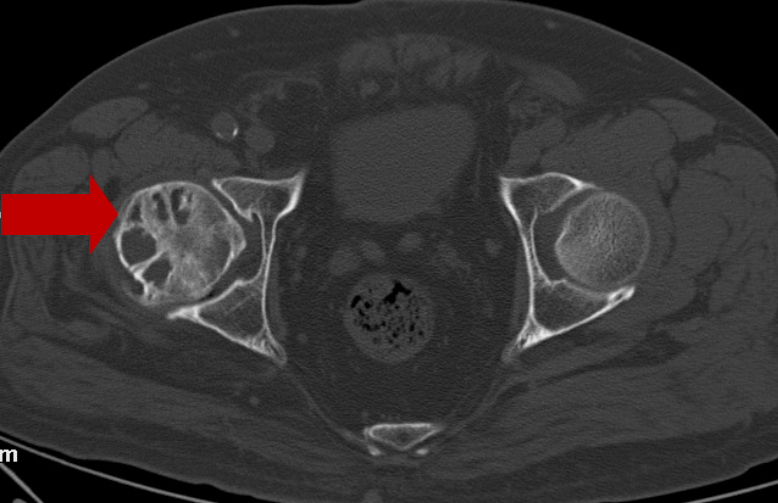

2020年8月6日CT:左股骨头囊样坏死区

分别于2020年8月7日、2020年10月12日行两次介入手术及相关米优最新版本综合治疗,左下肢酸痛不适消失,恢复正常生活。